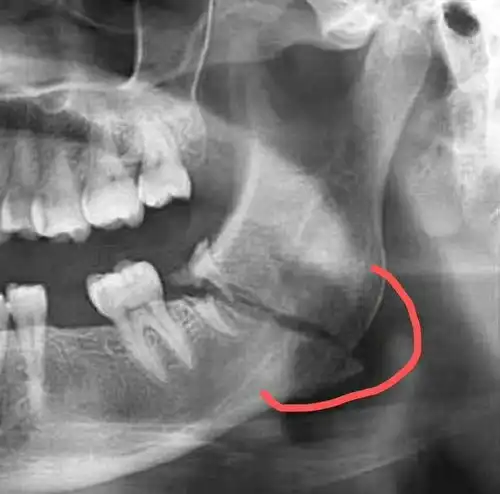

拔牙,一锤子下去,牙碎了骨也裂了